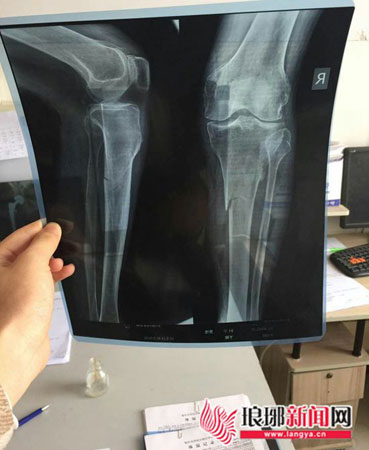

X线片显示老人的小腿骨折

受伤的老人,目前在住院治疗。